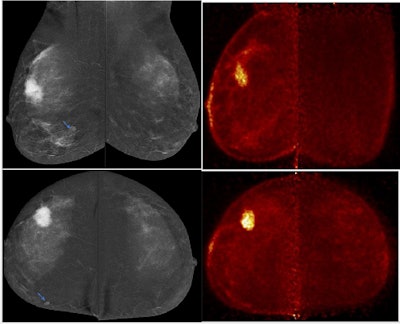

PEM detected contralateral malignancy missed in conventional mammography. Notably, there is a quantitative difference in uptake between both lesions, with the uptake of IDC in the right breast higher than ILC in the left breast. All figures courtesy of Dr. Aya Deabes et al and presented at EUSOBI 2025.

Image analysis of PEM examinations included morphological criteria, uptake pattern, lesion to background ratio (LTB), and maximum positron emission mammography uptake value (PUV max) assessment.

PEM detected multifocality in right breast and excluded multicentricity overestimated by contrast-enhanced mammography (left upper-outer quadrant focal heterogeneous non-mass enhancement was considered suspicious BIRADS-4). Left breast wide local excision revealed sclerosing adenosis and usual ductal hyperplasia. Follow-up revealed no residual suspicious lesions.

PEM performance in the detection of additional multicentric malignant lesions was impressive, with a sensitivity of 95.3%, specificity of 90.9%, and accuracy of 92.7%, the researchers noted. LTB and PUV max both performed very effectively as regards sensitivity and specificity in the detection of ILC, with sensitivity 93% and 95% and specificity 95% and 97%. PEM also showed impressive results in the detection of bilateral malignant lesions with a sensitivity of 100% and specificity of 86.1%, they pointed out.